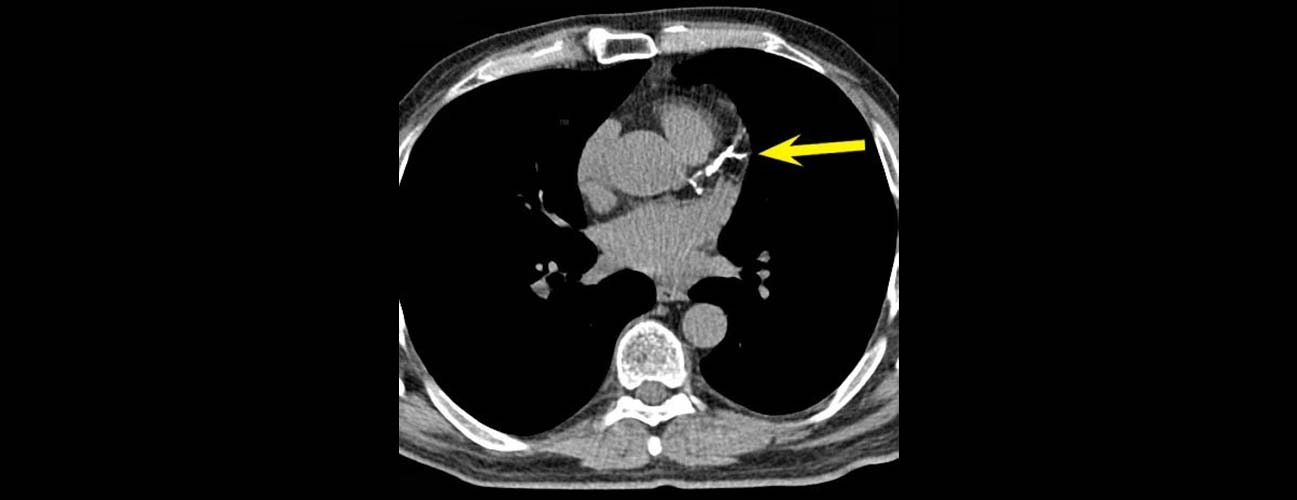

The calcium score test measures the amount of calcium in the walls of the coronary arteries. This is done using a special type of X-ray called a cardiac computed tomography (CT) scan. The test detects calcium deposits, which are signs of atherosclerosis or plaque buildup in the arteries. This plaque can restrict blood flow to the heart and increase the risk of heart attacks.

The test is sometimes called the CAC test, standing for Coronary Artery Calcium test. It uses a scoring system known as the Agatston score to quantify the amount of calcium. A higher score means more plaque and a higher chance of heart disease.